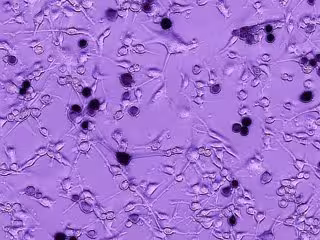

Archivo - Células de glioblastoma de un cerebro humano están creciendo. La adición del virus oncolítico Ebola-VSV produce infección tumoral y muerte celular, vista aquí como células negras. Con el tiempo, la infección se propaga a otras células de gliob

Archivo - Células de glioblastoma de un cerebro humano están creciendo. La adición del virus oncolítico Ebola-VSV produce infección tumoral y muerte celular, vista aquí como células negras. Con el tiempo, la infección se propaga a otras células de gliob - A VAN DEN POL - Archivo